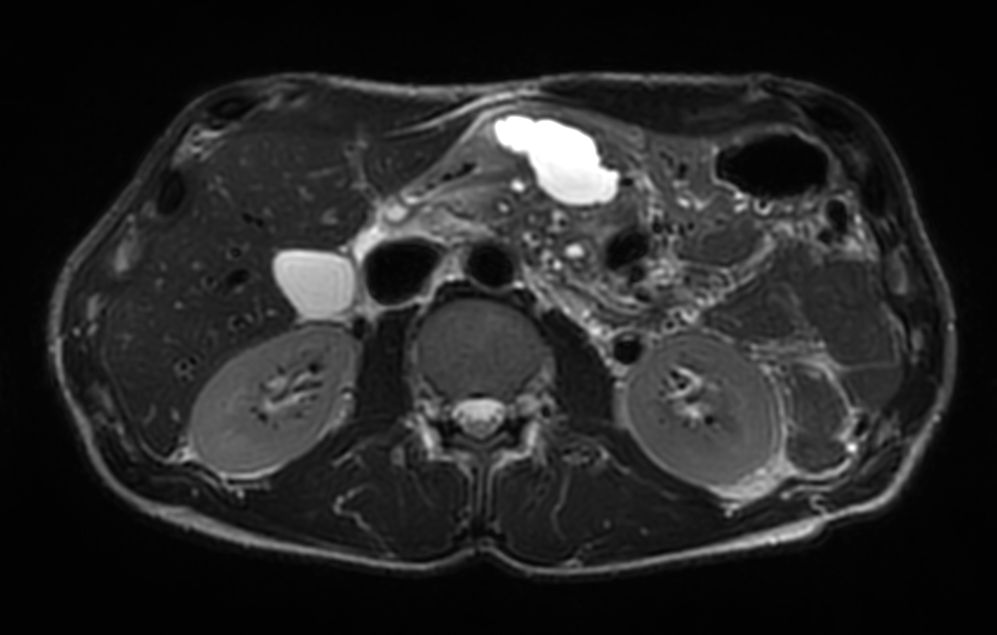

Axial T2w TSE MultiVane XD